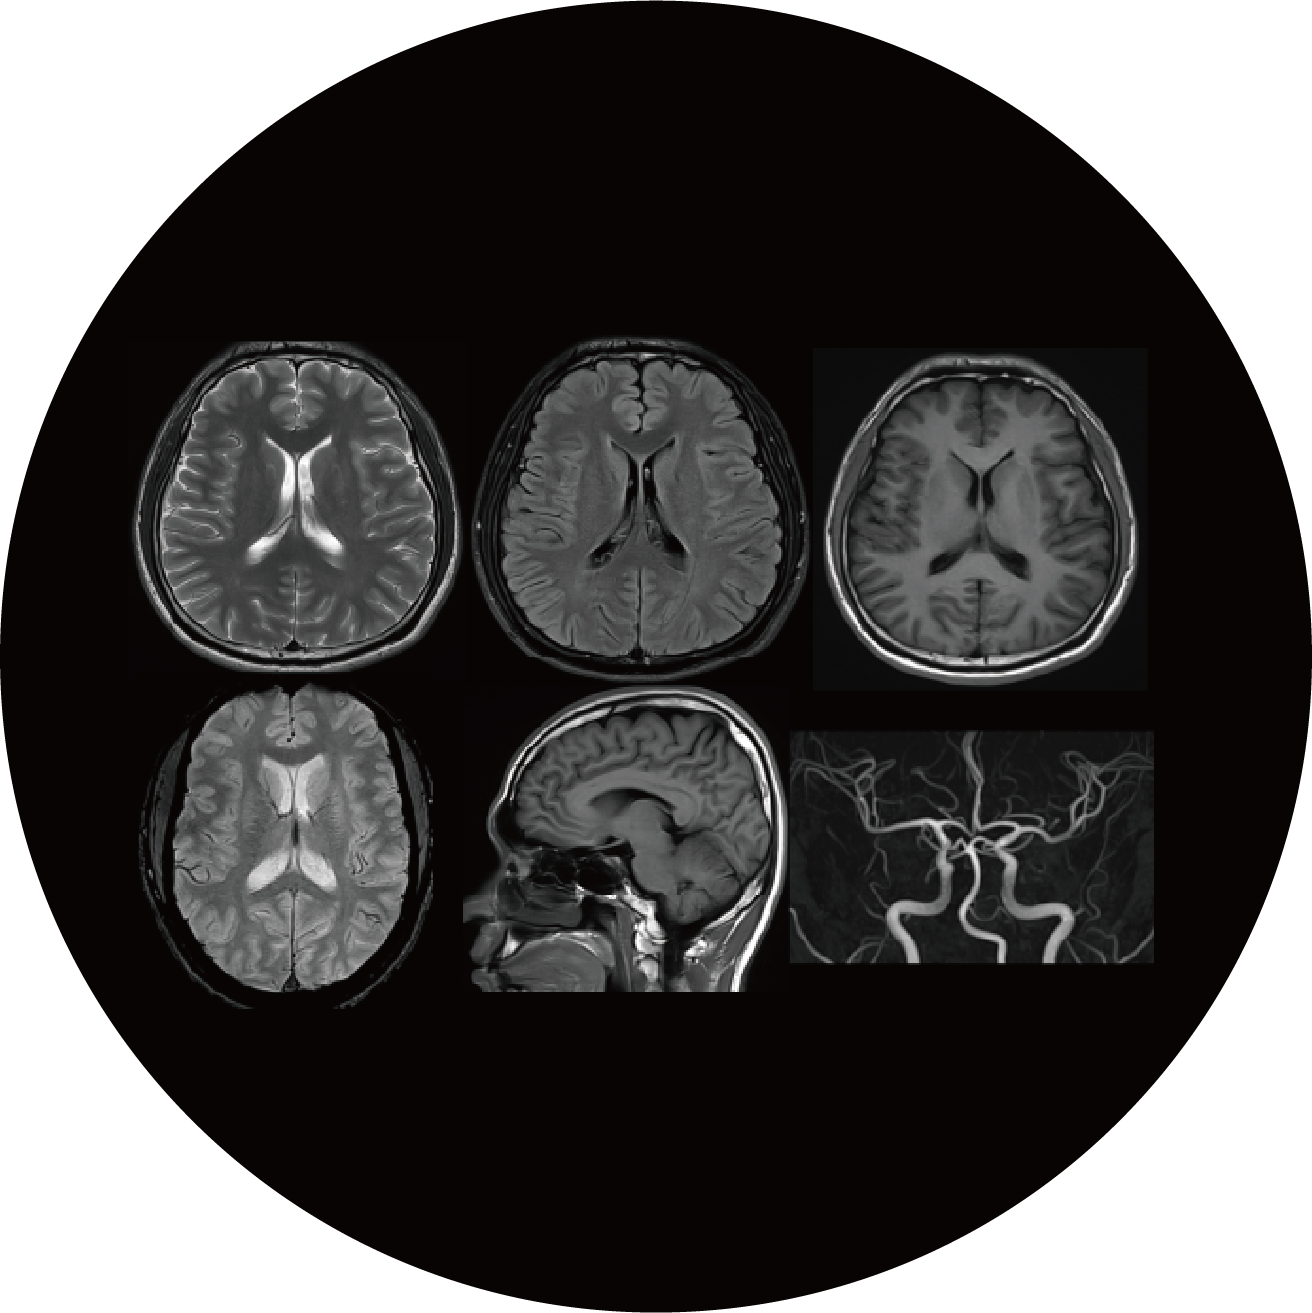

MRI

인체를 구성하는 물질의 자기적 성질을 측정하여 컴퓨터를 통해 재구성하고, 영상화하는 진단 방법입니다.

방사선 피폭 전혀 없음

대조도 우수

비침습적

기능적 인체 변화 측정 (병변 조기 발견)